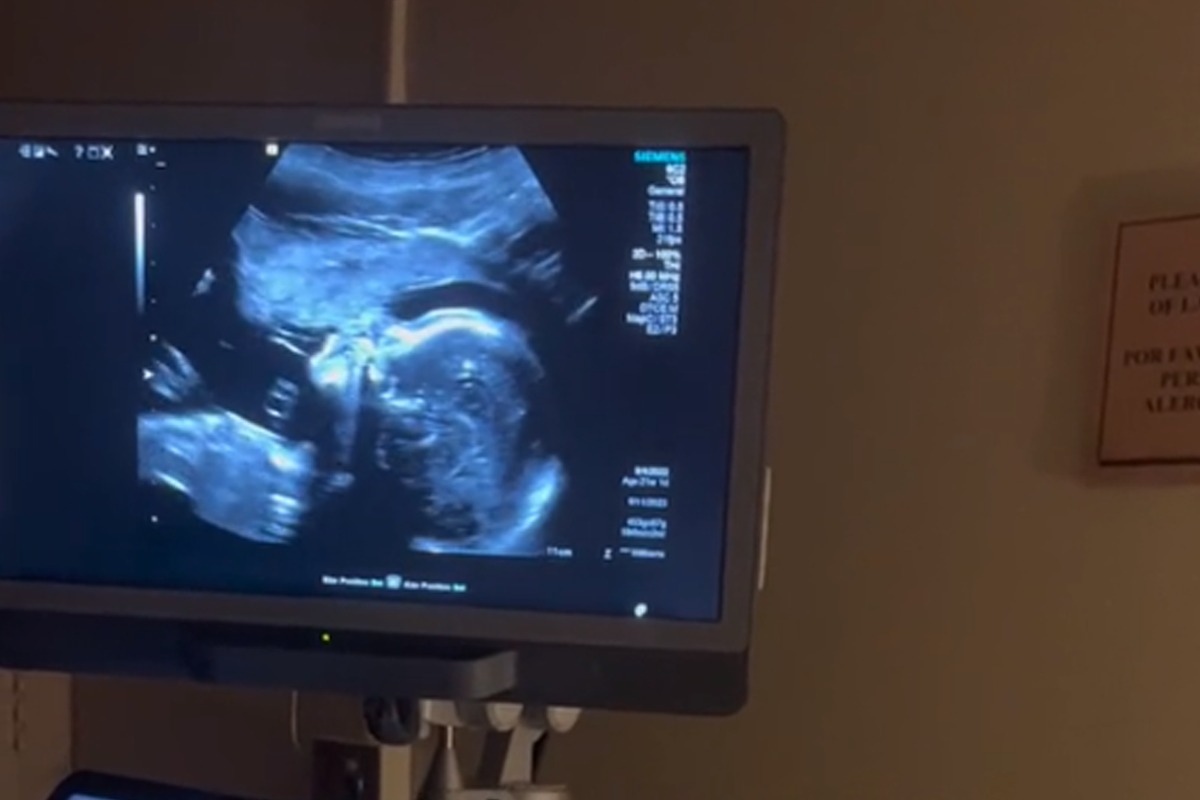

Fue a través de TikTok se difundieron las imágenes de este caso que ha dado la vuelta al mundo por la ternura que provocó en miles de usuarios. En el clip se puede apreciar a una madre cantando mientras le hacen un ultrasonido y el feto al escuchar la melodiosa voz de su madre también ‘gesticula’ como si le hiciera coro.

Ella no lo duda y procede a realizar la interpretación del tema. Inmediatamente, en el monitor se logra ver como el bebé mueve su boca como si estuviera cantando junto a su mamá. Todos en la sala quedaron sorprendidos por el particular suceso y uno de ellos dijo “Esto es asombroso”.